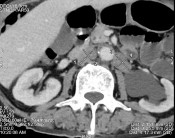

Bệnh nhân được chụp cắt lớp vi tính toàn thân, kết quả:

- Tuyến tiền liệt không to, không thấy tổn thương xâm lấn ra phía

ngoài.

- Nhiều tổn thương di căn lan toả nhu mô 2 phổi kèm theo lớp dịch

mỏng màng phổi 2 bên.

- Di căn hạch trung thất, hạch sau phúc mạc.

- Nhiều ổ đặc xương thứ phát ở xương sườn 4 phải, xương sườn 8 trái và nhiều đốt sống (thấy rõ ở D12, L2, L5).

Hình C. Hình ảnh chụp CT tại thời điểm kháng cắt tinh hoàn